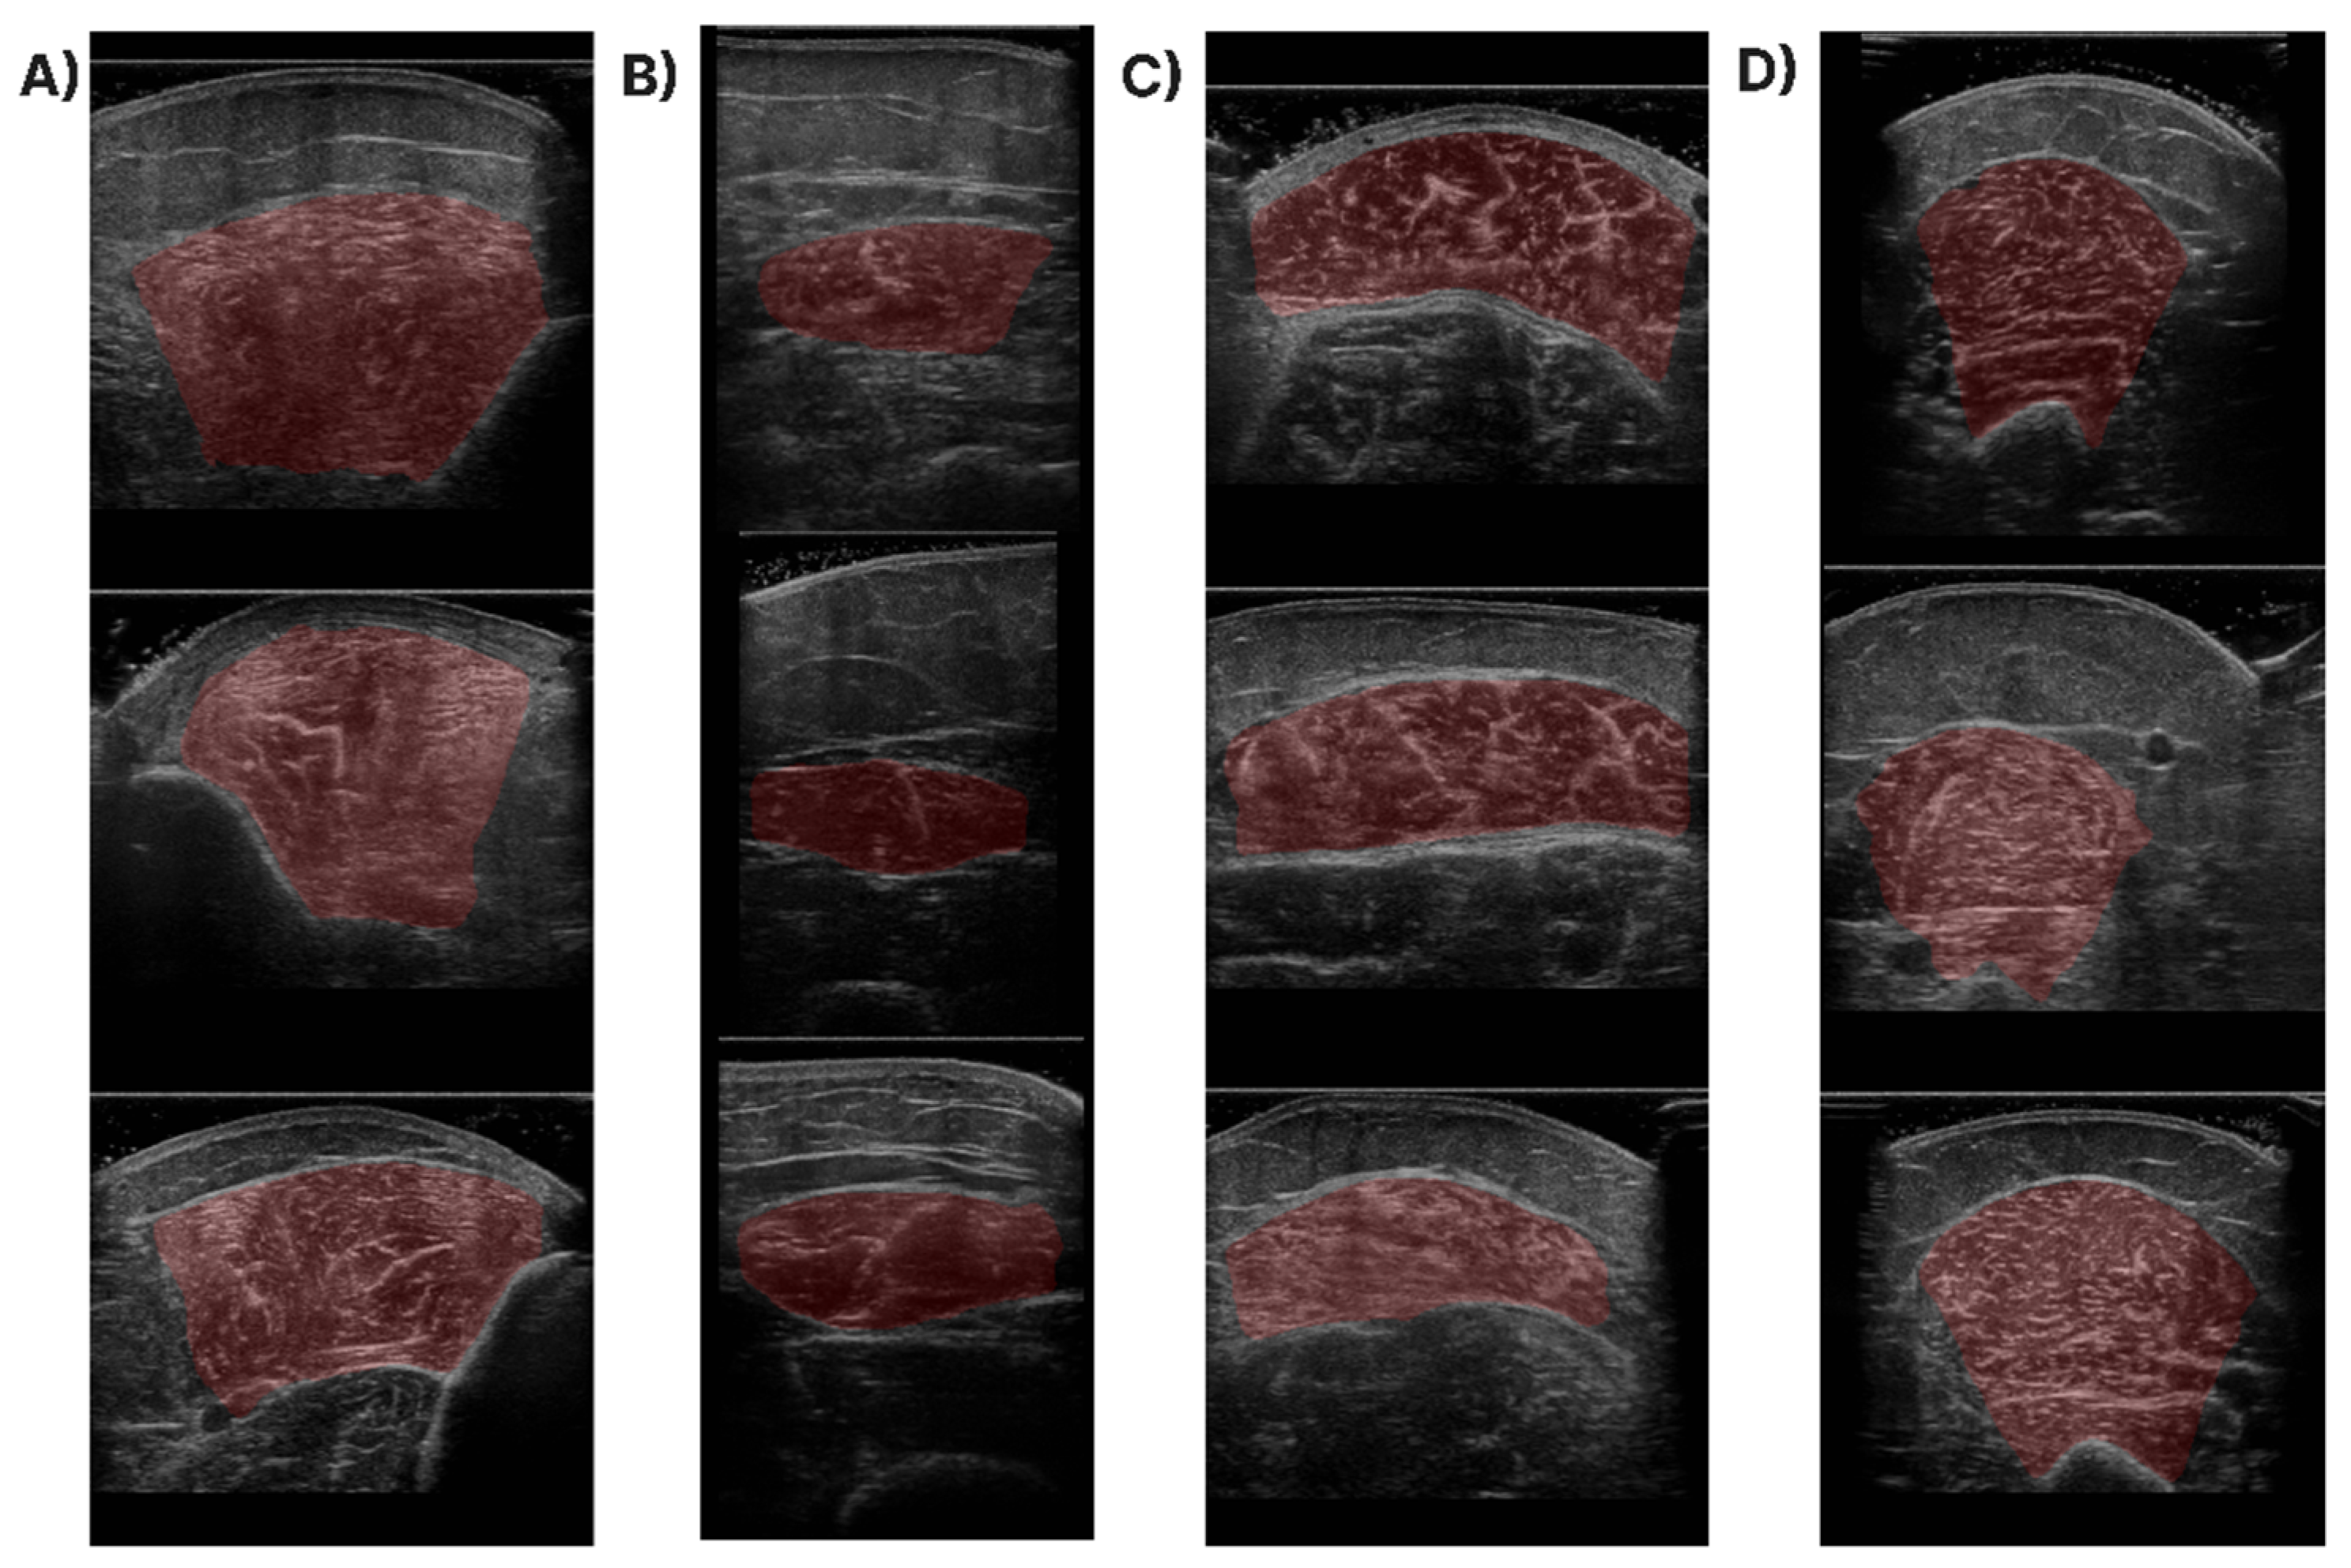

In Figure 1, samples of the studied muscles are presented for normal and high echogenicity images. It is observable in these images that the muscle aponeuroses, especially in the high echogenicity images, are hard to distinguish from the other muscle tissue, making the accurate localisation of the CSA more challenging.

Figure 1. Sample of ultrasound recordings with normal and high echogenicity. (A,E) shows images from the T.A., (B,F) shows images from the R.F., (C,G) shows images extracted from the GCM, and finally, (D,H) are images of the B.B.